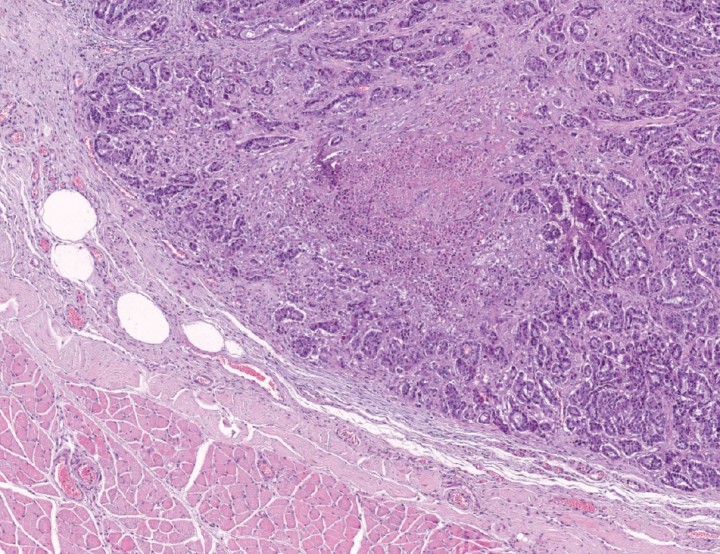

En la necropsia se observaron múltiples nódulos subcutáneos, blancos, firmes de 0,2 a 2 cm de diámetro en región lumbar, región esternal, espacios intercostales y glándulas mamarias e intramusculares de similar morfología. No se observaron lesiones macroscópicas en médula o columna vertebral. En el estudio histológico se observó que la mayor parte de la glándula mamaria había sido reemplazada por una neoplasia maligna no encapsulada, bien circunscrita, compuesta de células epiteliales dispuestas en cordones y túbulos (Fig. 1A). En algunas áreas, las células epiteliales se disponían en patrones sólidos con un gran centro necrótico (Fig. 1B). El índice mitótico y la anisocariosis eran elevados, observándose invasión de las células neoplásicas a vasos linfáticos y sanguíneos. En base a estos hallazgos se diagnosticó un carcinoma tubulopapilar simple, con áreas de comedocarcinoma, de alto grado (grado III).[ Mills SW, Musil KM, Davies JL, Hendrick S, Duncan C, Jackson ML, et al. Prognostic value of histologic grading for feline mammary carcinoma: a retrospective survival analysis. Vet Pathol, 2015; 52(2): 238-249. [PubMed] ] En el pulmón y músculo esquelético de los miembros posteriores, se observaron focos neoplásicos, muchos de ellos mostrando un patrón de comedocarcinoma (“nidos” sólidos con focos necróticos) (Fig. 2). Asimismo, había una evidente invasión vascular, principalmente en pequeñas arteriolas (Fig. 3). Se observó un nódulo metastásico grande, bien circunscrito, no encapsulado en la médula espinal (segmento L1-L2). Las células neoplásicas, que mostraron morfología de comedocarcinoma, expandían la sustancia blanca y comprimían la gris (Fig. 4A). Por su parte, las células neoplásicas presentes en todos estos órganos eran intensamente positivas para citoqueratina y negativas para vimentina y actina, lo que es consistente con un diagnóstico de carcinoma simple (Fig. 4B).

<p>Imagen microscópica de la médula espinal a nivel de L2. (A) Se aprecia metástasis intramedular de carcinoma mamario (HE 20x). (B) Se observan células neoplásicas intensamente positivas para citoqueratina. Inmunohistoquímica para CK AE1/AE3, contrateñido con hematoxilina x40.</p>

Imagen microscópica de la médula espinal a nivel de L2. (A) Se aprecia metástasis intramedular de carcinoma mamario (HE 20x). (B) Se observan células neoplásicas intensamente positivas para citoqueratina. Inmunohistoquímica para CK AE1/AE3, contrateñido con hematoxilina x40.